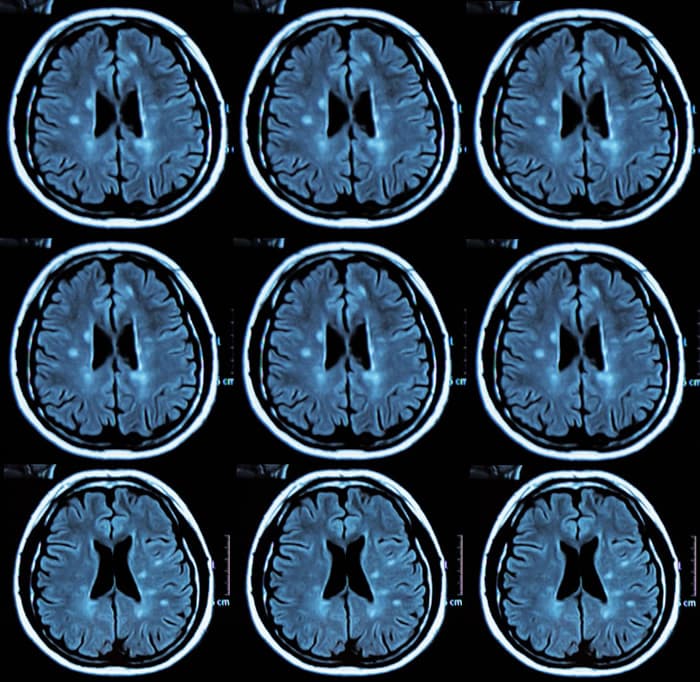

Episodio 1: Descripción de la Esclerosis Múltiple

En este primer episodio de Charlas de Esclerosis Múltiple nuestro neurologo especialista nos describe lo que es la EM y sus diferentes variantes.